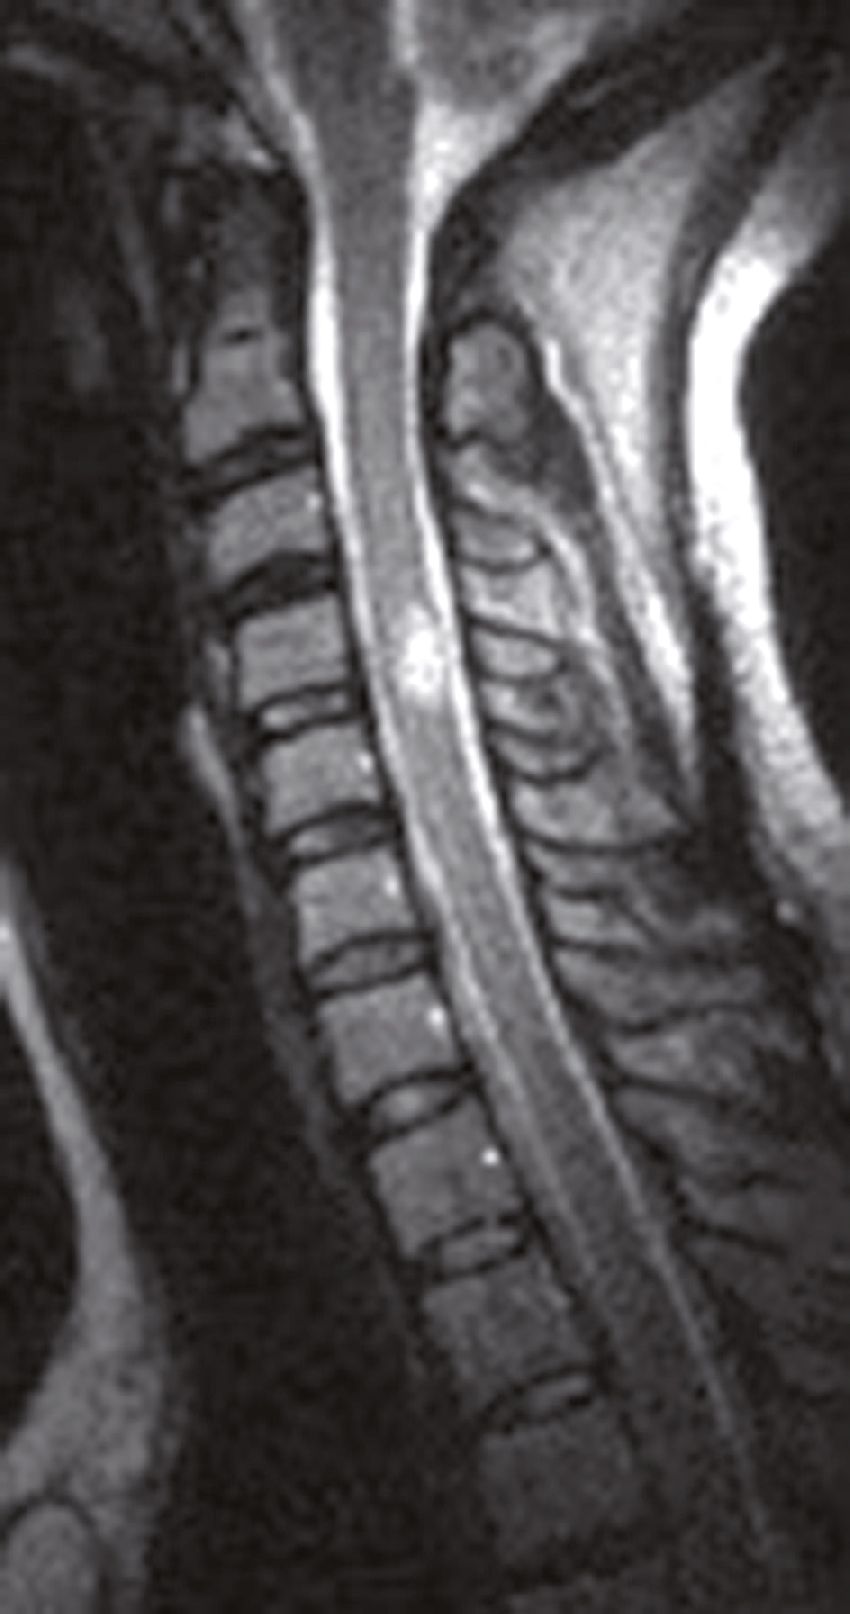

Question 5 – QRU

Une IRM médullaire cervicale est réalisée (fig. 31.6). Quelle(s) est (sont) l’(les) affirmation(s) exacte(s) correspondant à cette planche d’IRM ?

L'image montre une IRM de la colonne cervicale. On peut voir les vertèbres cervicales empilées les unes sur les autres, séparées par des disques intervertébraux. L'IRM permet de visualiser les structures internes de la colonne vertébrale, y compris la moelle épinière et les tissus environnants. Les vertèbres apparaissent comme des blocs rectangulaires sombres, tandis que la moelle épinière est visible comme une structure plus claire au centre. Les disques intervertébraux sont les espaces plus sombres entre les vertèbres. Cette image permet de détecter des anomalies telles que des hernies discales, des compressions de la moelle épinière ou d'autres pathologies affectant la fonction neurologique. L'IRM est un outil précieux pour les médecins car elle fournit des images détaillées sans utiliser de rayonnement ionisant. Les images obtenues par IRM sont cruciales pour évaluer l'état de la colonne vertébrale et planifier les interventions médicales nécessaires. Les détails observables, comme la forme et la position des vertèbres et des disques, sont essentiels pour une évaluation approfondie.

- A 584hypersignal extramédullaire à hauteur de C4-C5

- B hypersignal extramédullaire à hauteur de C3-C4

- C hypersignal intramédullaire à hauteur de C3-C4

- D hypersignal intramédullaire à hauteur de C4-C5

- E hypersignal intramédullaire à hauteur de C5-C6